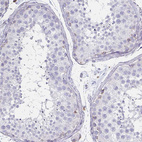

Immunohistochemistry analysis in human lymph node and testis tissues using AMAb90616 antibody. Corresponding STX7 RNA-seq data are presented for the same tissues.